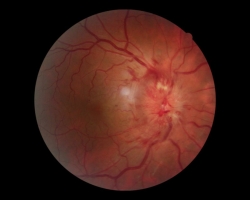

- OD : œdème papillaire avec hémorragies

- OG : FO normal

FO : cf. images jointes